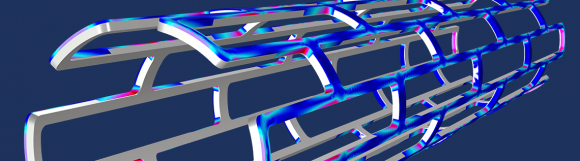

Las aplicaciones biomédicas suelen ser de naturaleza multifísica, desde los implantes de bombas mecánicas en el corazón, a dispositivos de almacenamiento de vacunas, hasta analizadores hematológicos. Por lo tanto la simulación multifísica puede ayudar a revolucionar la manera en el que los dispositivos y procesos biomédicos son diseñados y analizados.

En este artículo... Noticia completa ⇒ |